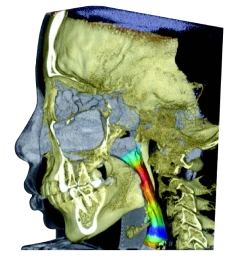

- Анализ пазух и дыхательных путей

- Анализ дыхательных путей и ВНЧС